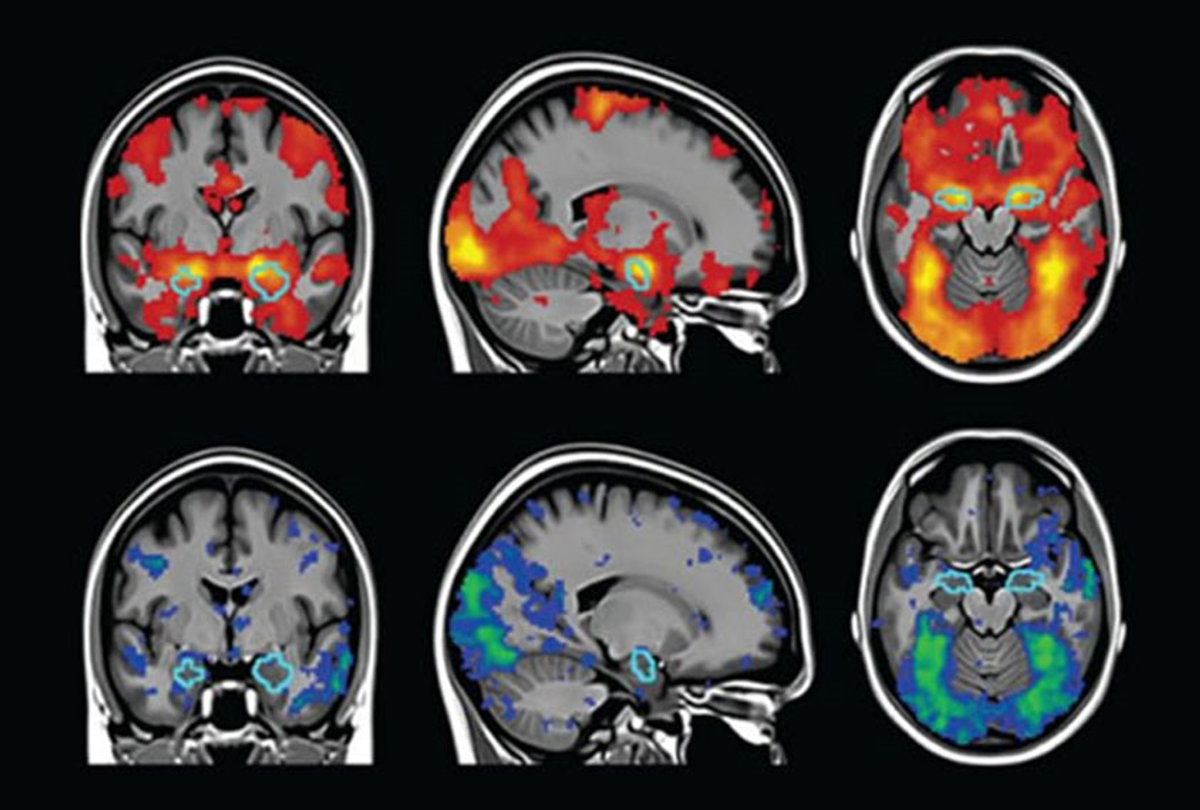

- 환자의 체위를 변화시키지 않고 횡단면(axial), 시상면(sagittal), 관상면(coronal)의 영상을 얻을 수 있음.

기능적 자기공명영상 (Functional magnetic resonance imaging, fMRI)

: a non-invasive technique for examining brain activity (that creates a dynamic record of metabolic activities over time)